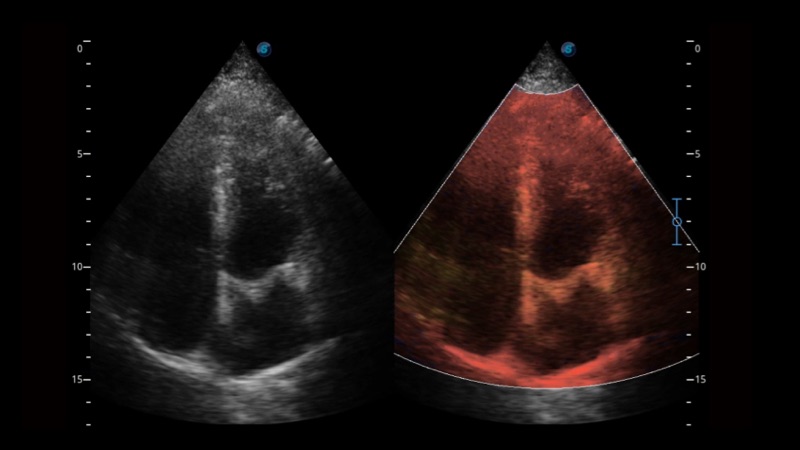

组织多普勒

组织多普勒成像功能,可提供心肌运动速度和其他临床信息,使临床医生能够分析和比较患者心脏不同部位的运动。

造影成像

造影成像功能和定量分析工具包使医生能够更好的评估血流灌注情况。独特的动态声压控技术有效控制造影剂的声压,保证更长的造影剂持续时间,更好的观察病变灌注的延迟相位。

临床图像